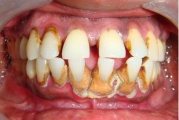

Krooniline parodontiit

Krooniline parodontiit on mikroobide poolt põhjustatud hammaste tugikudede põletik, mille tulemusena tekib progresseeruv alveolaarluu (nähtav röntgenograamil) ja periodontaalligamendi destruktsioon, igemetaskute moodustumine, igeme retsessioon või mõlemad kahjustused kombineeritult. Loe edasi »

Sümptomid:

- igemed veritsevad (19)

- igemed punetavad (21)

- ige on paistes (mädapunn)

- igemed on tursunud/vohavad (17)

- igemed on valulikud (19)

- igemepiir on taandunud (3)

- luu destruktsioon (5)

- hamba kinnitussidemete kadu (3)

- puudulik suuhügieen (5)

- igemepealne hambakivi (5)

- igemealune hambakivi (4)

- igemetaskust eritub mäda (3)

- halb hingeõhk / suu haiseb (12)